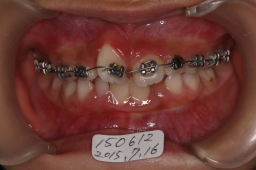

2015年07月16日

かなり右前歯(11番)の捻転が改善してきました。